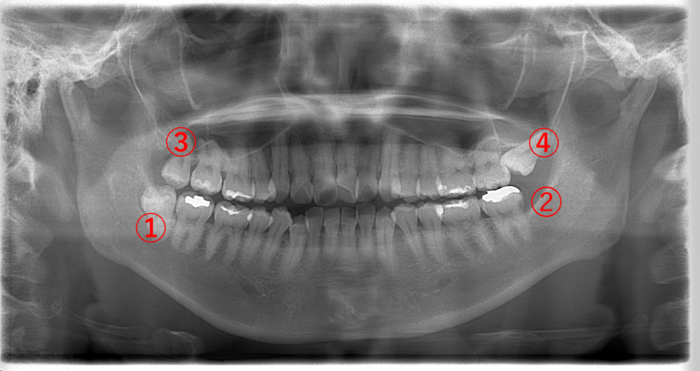

| 年齢・性別 | 24歳・女性 |

|---|---|

| 主訴 | 右上の親知らず(画像③)が急に痛み始めた。 |

| 歯ブラシ | 毎日歯を磨いている。 親知らずまでは磨けてない。 |

画像③の親知らずを見てみると黒く透けています。虫歯になると歯が溶けて柔らかくなるので、レントゲンでは黒く写ります。虫歯が歯の神経に達すると痛みが強くなります。

③の親知らずを抜歯して、①の親知らずも抜きたいところですが、③の親知らずの痛みが強いこともあり、一緒に抜歯せずに後で③の親知らずを抜く方が良いと説明しました。

親知らず以外の歯に関してはかなりきれいに磨けていました。奥にある親知らずの歯ブラシが難しいことがわかります。

痛みが強い歯は、その状態により対合する歯を一緒に抜くことができないこともあります。